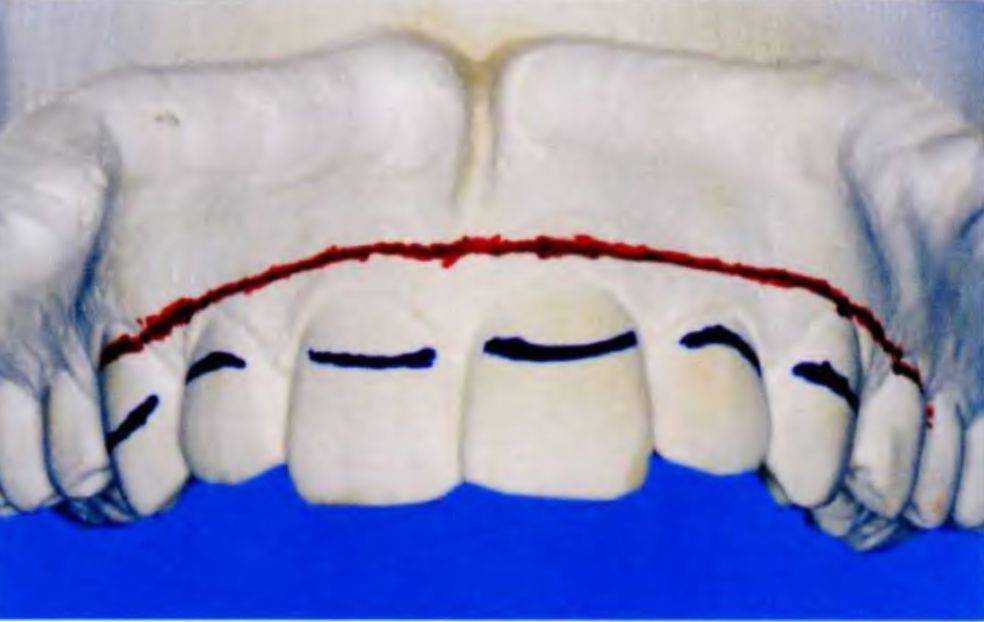

Линию губы и линию улыбки для верхней губы переносят на модель (рис. 6-45и и 6-45v). Затем анализируют зубы и десну безотносительно улыбки пациента, но при произнесении им длинного звука «и». Определяют симметрию десневого контура.

Рис. 6-45u. Линию губы (синий цвет) наносят на модель верхней челюсти

Рис. 6-45v. Линию улыбки (красный цвет) наносят на модель верхней челюсти

Контур десны отмечают в области каждого переднего зуба, определяют исходный и эстетически предпочтительный контур, уровень и зенит. Полученные данные и ориентиры можно использовать при планировании изменения края десны (рис. 6-47).